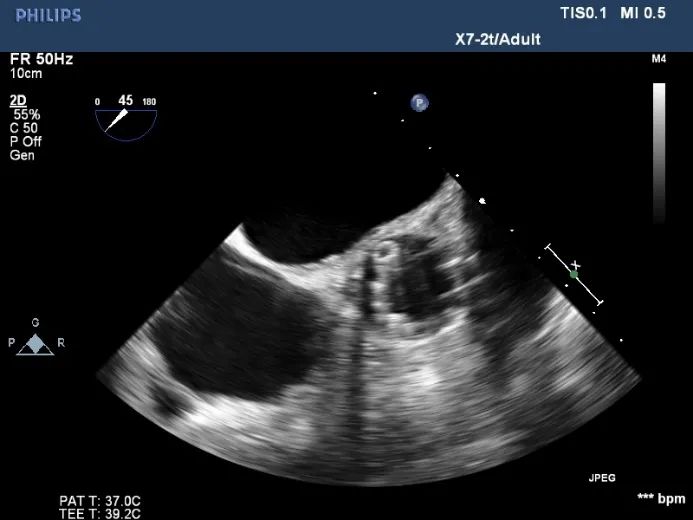

超声影像

瓣膜工作状态良好,极微量瓣周漏

Vmax 1.75m/s,PG 14mmHg